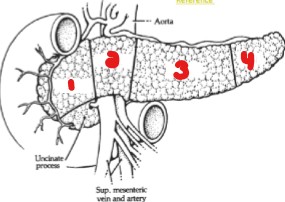

Label the parts of the pancreas.

Head

Neck

Body

Tail

What structures does the pancreas lie between?

Duodenal loop

Splenic hilum

The tail of the pancreas lies anterior to which 2 structures?

Splenic hilum

Upper pole of the left kidney